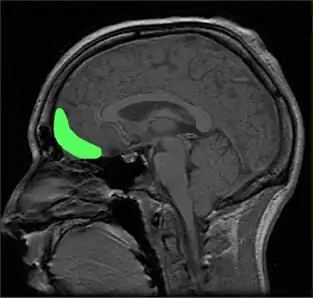

| Illustration of lateral view of the right side of the brain showing the frontal lobe, other lobes of the brain, and the cerebellum | |